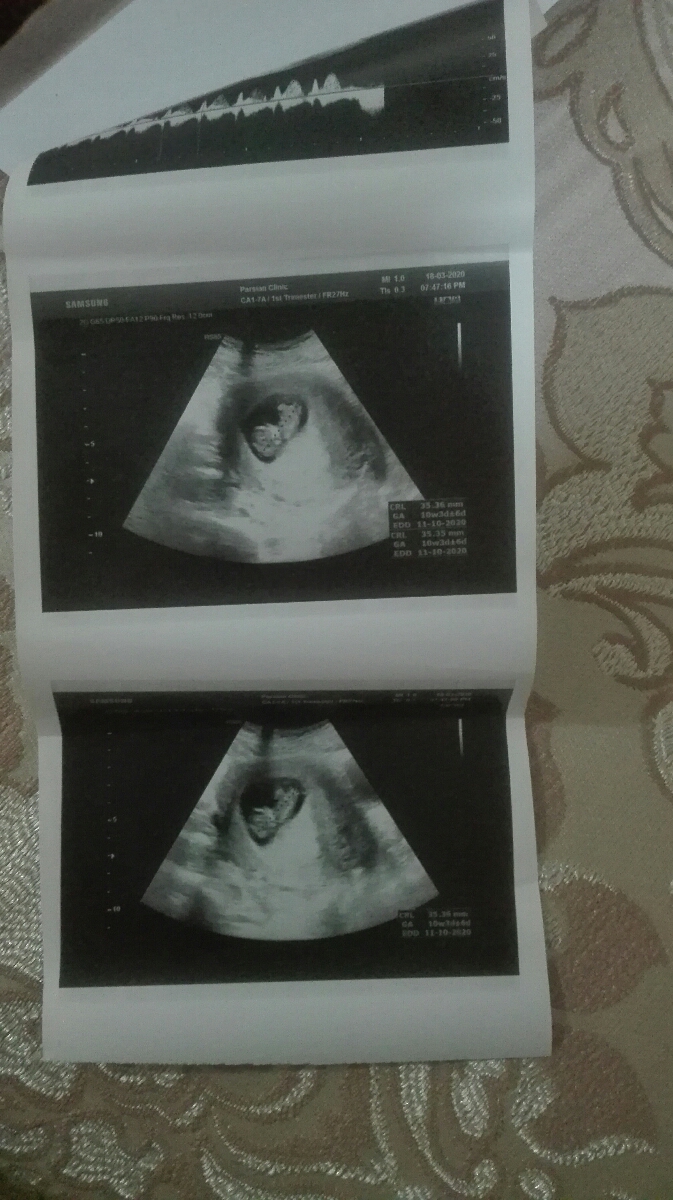

سلام مامان گلا،پیشاپیش سال نو همگی مبارک.امروز عصری من لک دیدم سریع رفتم دکتر فرستاد سونو .عکس سونو هم فرستادم براتون.استراحت مطلق داد بهم و شیاف پروژسترون.گفت جفتت پایینه نباید تکون بخوری،کیا اینجوری بودن تو بارداری میشه منم راهنمایی کنید مرررسی..

رفتم سونو صدای قلبشو شنیدم آرومتر شدم اما نگرانم

چرا سن بارداریت با سن بارداری اوما یکی نیس

درستش کن عزیزم الان باید بزنی ۱۱ هفته

ده هفته و سه روزه سونوت